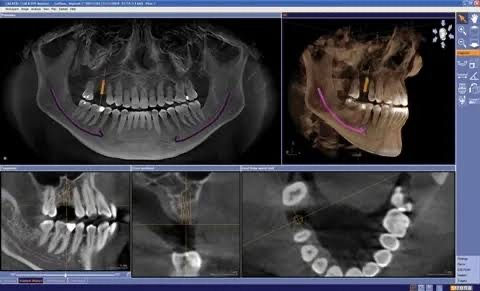

When it comes to successful dental implant placement, precision and planning are everything. Traditional X-rays provide a limited, two-dimensional view — but dental implants require a much deeper understanding of your bone structure, nerves, and surrounding anatomy. This is where 3D CBCT imaging (Cone Beam Computed Tomography) steps in — and it’s transforming how leading clinics like Advanced Dental Care Center in Chandigarh approach implant dentistry.

CBCT stands for Cone Beam Computed Tomography, a specialized imaging system that creates detailed 3D scans of your teeth, jawbone, sinuses, and nerves. Unlike traditional X-rays, which only provide flat images, CBCT gives your dentist a complete 360-degree view of your oral anatomy.

This allows for precise diagnosis, planning, and placement of dental implants with unmatched accuracy.

The 3D images help Dr. Anshu Gupta visualize the exact location and density of the jawbone, as well as the position of nerves and sinuses. This allows her to place implants with microscopic precision, reducing the risk of complications.

With detailed CBCT scans, Dr. Gupta can plan:

• The exact angle and depth of implant placement

• Whether bone grafting is needed

• The size and type of implant to use